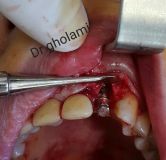

معرفی سیستم SPI همراه با جراحی زنده و Immediate Loading - آبان ۹۵

جراح وسخنران : استاد دکتر غلامعلی غلامی